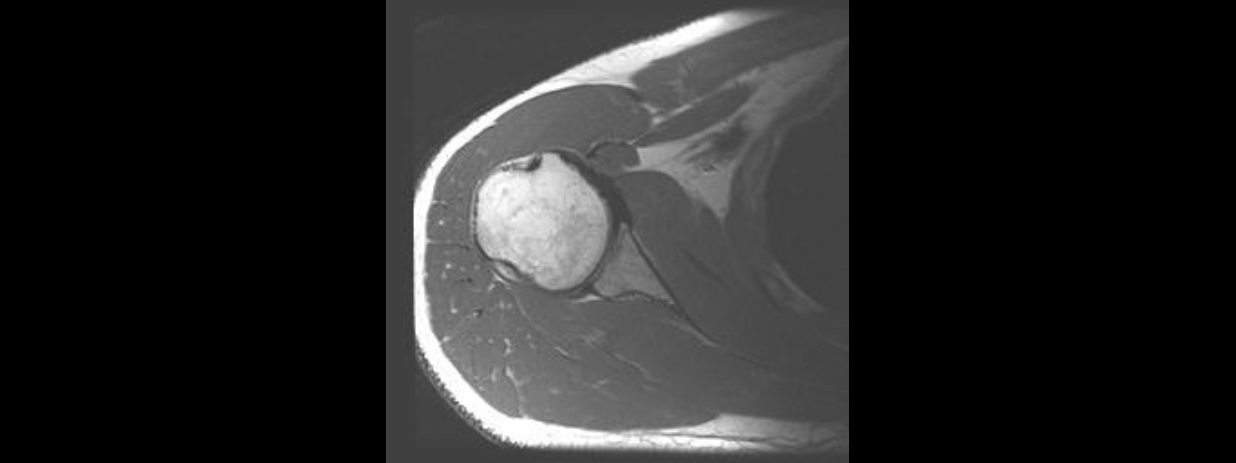

Resonancia Magnética

Es un análisis seguro e indoloro en el cual se utiliza un campo magnético y ondas de radio para obtener imágenes detalladas de los órganos y las estructuras del cuerpo.

Se pueden colocar pequeños dispositivos, llamados espirales, en la cabeza, el brazo o la pierna u otras áreas que se vayan a estudiar. Estos dispositivos ayudan a enviar y recibir las ondas de radio y mejoran la calidad de las imágenes.